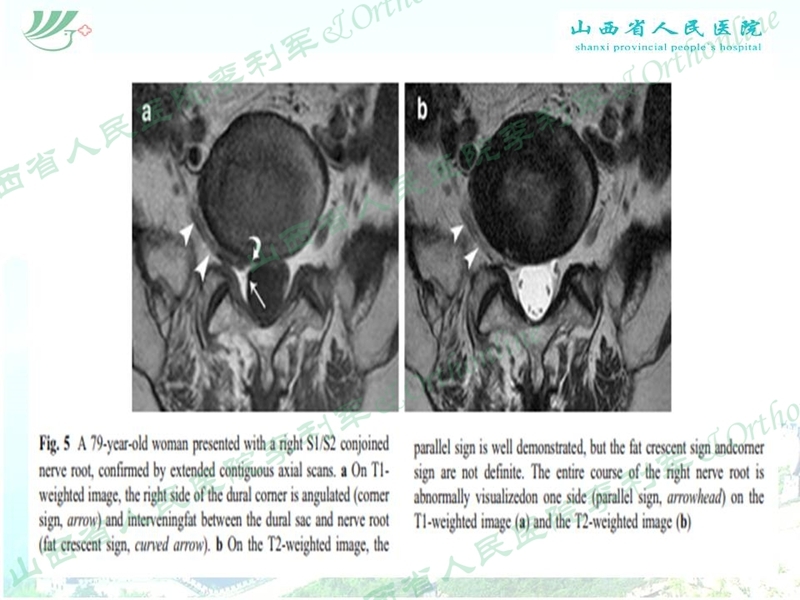

山西省人民医院李利军医生根据自己临床遇到的部分病例,归纳常见的特殊腰椎间盘突出为:高度游离间盘突出,伴有钙化的间盘突出,巨大间盘突出,复发间盘,极外侧间盘突出,易误诊为肿瘤的间盘突出,伴有神经变异的间盘突出等;并根据自己的临床体会对以上特殊类型间盘突出的孔镜治疗作了一些技术总结,以期达到抛砖引玉的作用,并等到大家的批评和指导。